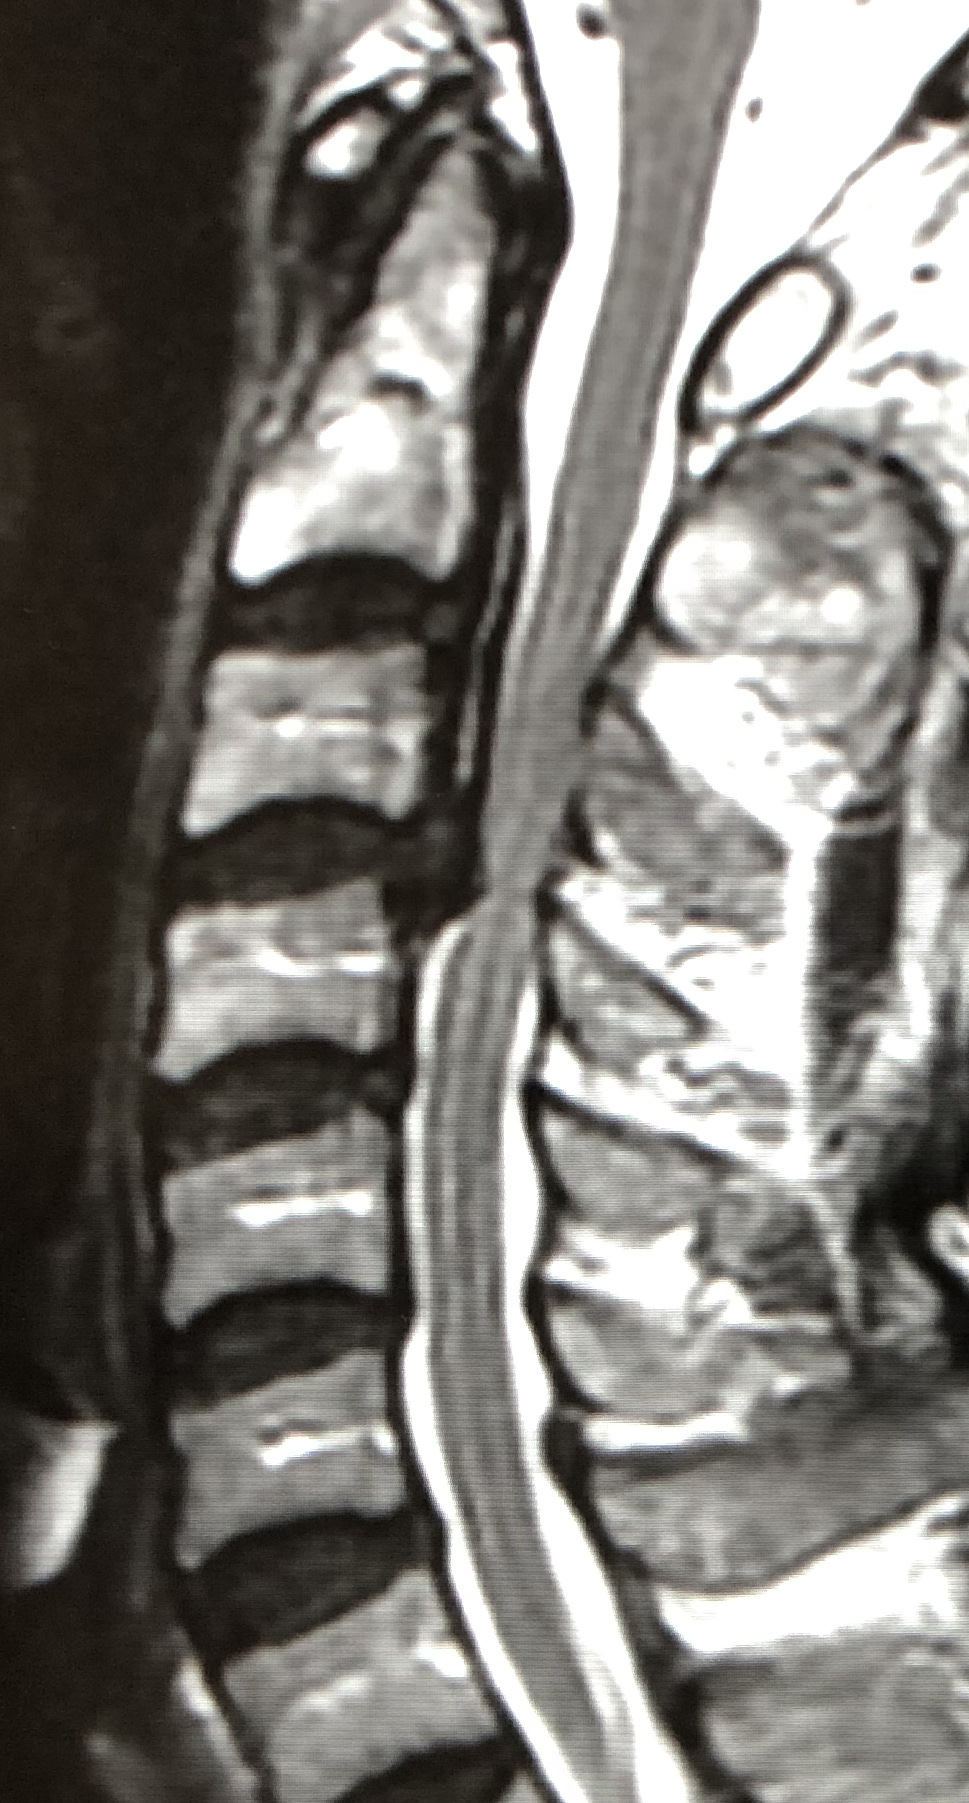

eXtreme Lateral Interbody Fusion(XLIF)は、主に左脇腹からの小皮切で腰椎に側方からアプローチし、脊椎前方に十分な骨移植を行ない脊椎の矯正固定を行なう手術方法です。脊柱管内には一切触れずにす椎間板の高さを増大させてすべりを矯正し、間接的な神経の除圧が可能です。

| 術前 | 術後 | |

| MRI |

|